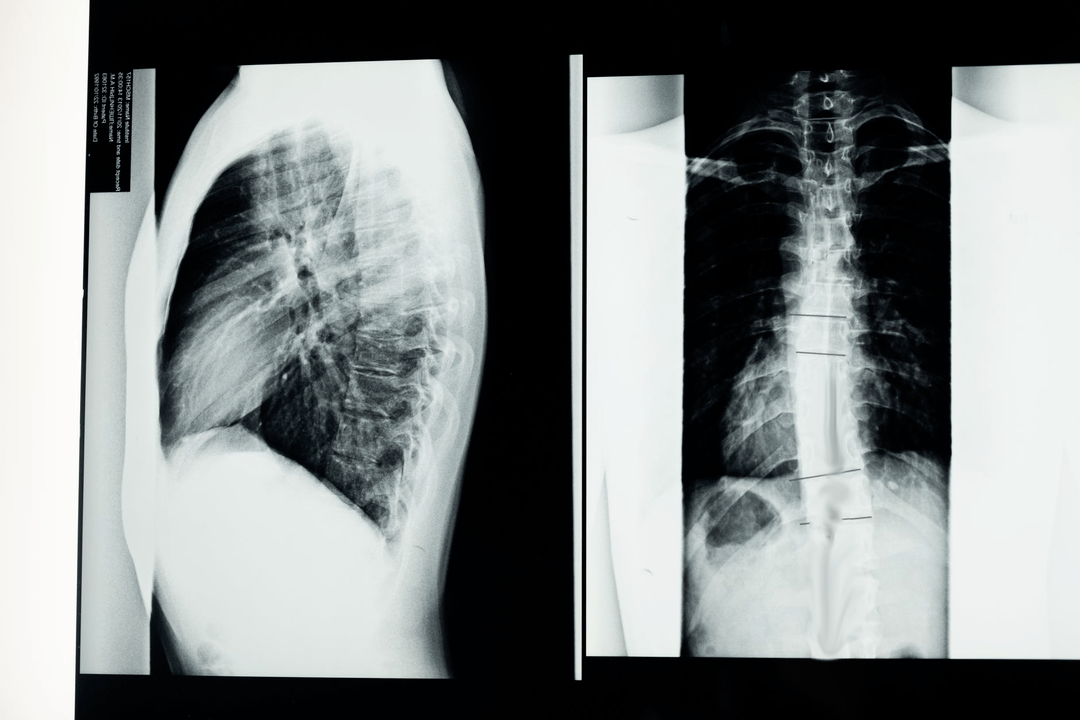

Před zahájením diagnostických studií neurolog shromáždí anamnézu pacienta a pečlivě prostuduje jeho stížnosti. Osteochondróza má společné příznaky s některými dalšími onemocněními, takže je důležité umět odlišit patologie. Rentgenové studie pomohou potvrdit diagnózu osteochondrózy: radiografie, myelografie a počítačová tomografie.

Průzkumný rentgenový snímek umožňuje získat rentgenový snímek páteře nebo její části. Tímto způsobem může lékař určit místo postižené onemocněním. Pro názornost si vysvětlíme, jak lze osteochondrózu rtg určit: na snímku bude patrné zúžení meziobratlové ploténky, přítomnost kostních výrůstků (osteofytů) nebo změna tvaru segmentu páteře.